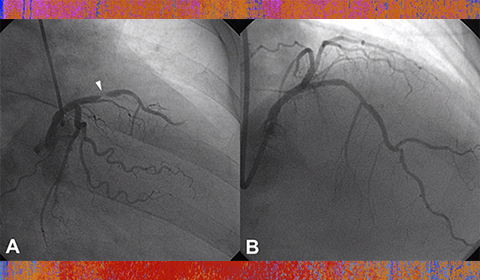

In the hands of experienced operators and high-volume transradial catheterization centers, transradial coronary angiography and intervention offer improved patient comfort, decreased access-site complications, and lower costs without compromising procedural success or long-term outcomes.